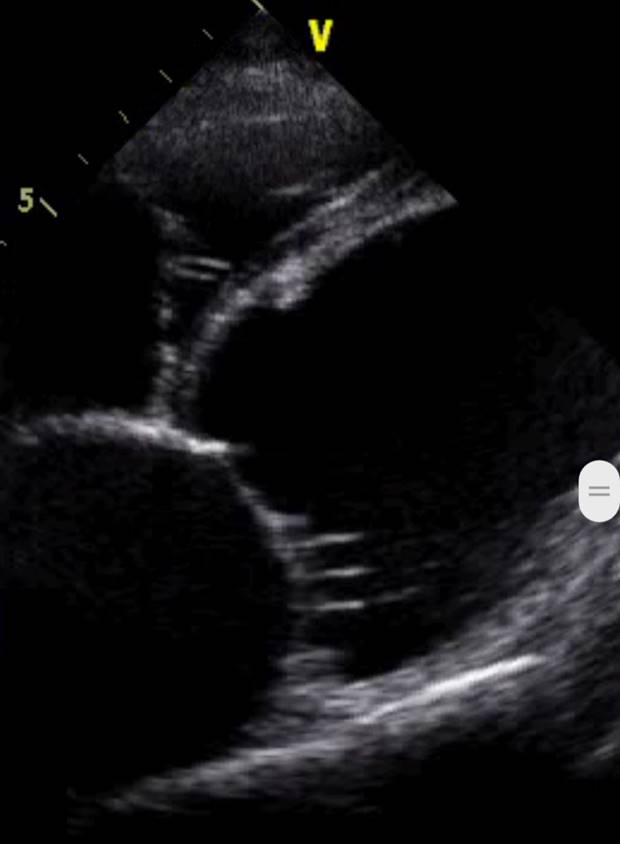

Окончательный диагноз ставится на основании ультразвукового исследования сердца (ЭХО КГ).